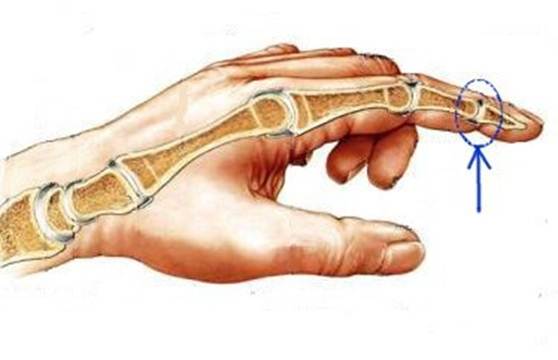

S: Стрелка указывает на art. Interphalangea manus

S: Стрелка указывает на art. Interphalangea manus

S: Стрелка указывает на art. Interphalangea manus